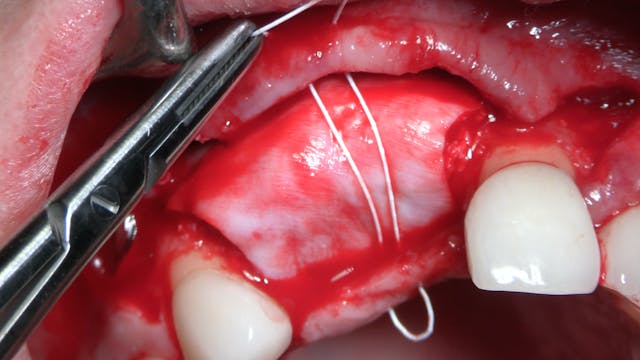

Passive Flap Closure of Implant Sites with Horizontal Mattress and PTFE sutures

by Dr Sascha A Jovanovic